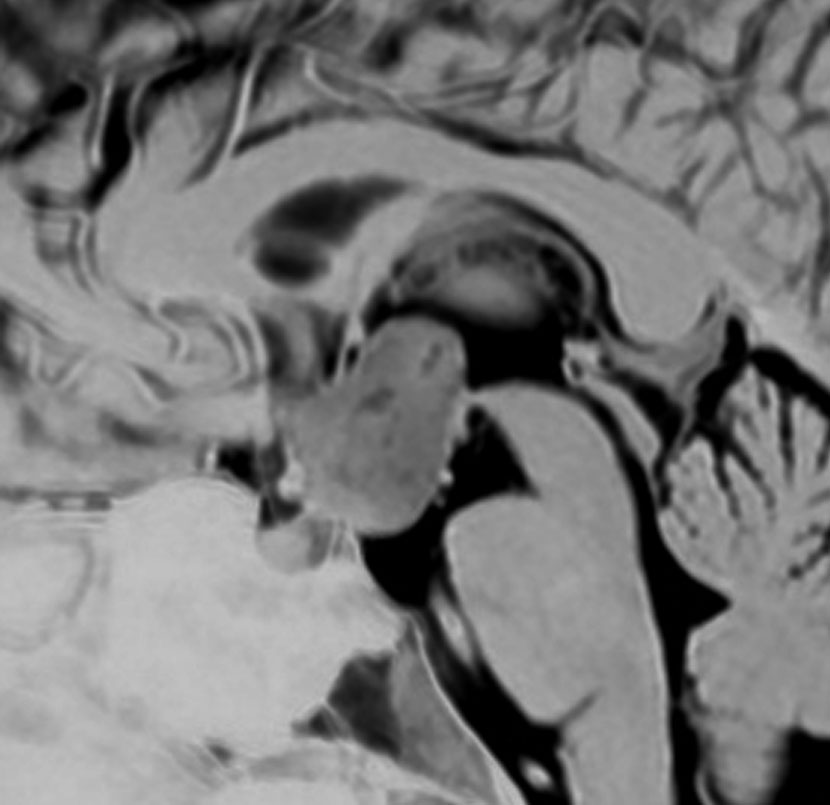

2歳の時に歩行障害で転倒しやすくなって発症しました。巨大な小脳虫部の毛様細胞性星細胞腫です。後頭下開頭で亜全摘出して,翌年,残っていた小さな残存腫瘍を全摘出しました。

cerebellarpilo3cerebellarpilo4

16歳になってとても元気に学校へ通っています。こんな小脳でもちゃんと歩けるようになります。残っているわずかな小脳機能を手術で守ることはとても難しいと言えます。